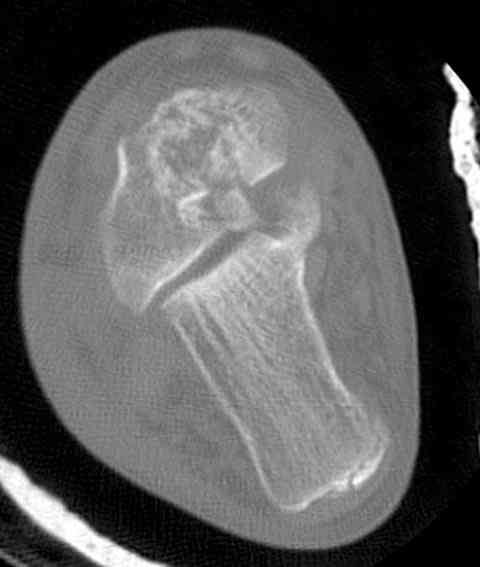

Случай с множественным оскольчатым переломом тарана оперированный из

двойного доступа.

Имя     : talar fx.ct 6.jpg

Тип     : image/jpeg

Размер  : 18105 байтов

Описание: отсутствует

Url     : http://weborto.net:8080/pipermail/ortho/attachments/20070615/61a2112e/attachment-0012.jpg